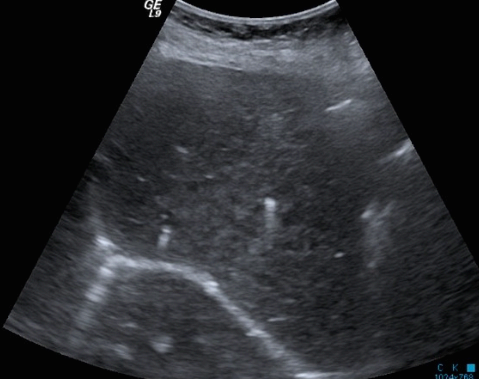

US finding

- comet-tail artifact

- 크기가 작고 간전체에 흩어져 보임(multiple small hyperechoic lesion)

- echos scattered through the liver ( <1cm )

bile duct hamartomas ④ caroli disease